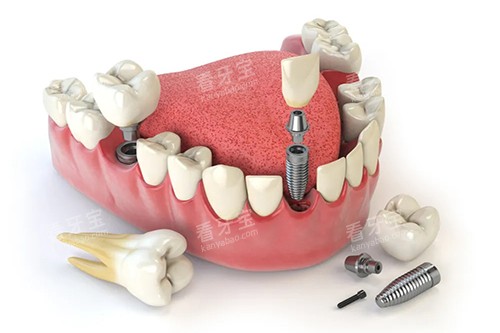

在种牙方面,医院拥有多种可靠的种植系统,如瑞士 ITI 种植系统、德国 BEGO 种植系统等,能够满足不同患者的需求。

医生们根据患者的口腔情况和经济状况,为患者推荐合适的种植系统,并制定个性化的种植方案。

在手术过程中,医生们熟练掌握种植技术,确保种植手术的安心和成功。

术后,医院还会为患者提供详细的护理指导,帮助患者尽快修复。